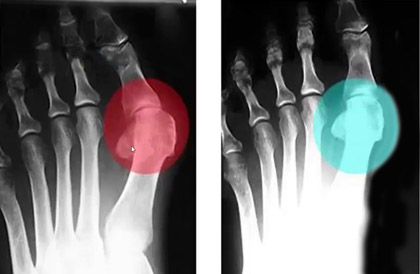

До использования

После 1,5 месяца использования шины Relax Foot

С целью устранения Hallus valgus (бурсита) и негативных симптомов, сопровождающих деформацию ступней, успешно применяется магнитотерапия. Магнитотерапия – уникальный метод физиотерапевтического лечения с помощью воздействия на организм постоянным, переменным или бегущим магнитным полем. Процедура является безопасной и не вызывает болезненных ощущений.

Чтобы купировать воспалительный процесс, достаточно использовать магнитную шину Relax Foot ежедневно в течение 3-5 часов. Это способствует не только выравниванию фаланг пальцев и уменьшению деформации, но также благодаря воздействию магнитов происходит стимуляция нервных окончаний, повышается тонус тканей, улучшается кровообращение. Relax Foot фиксирует большой палец в нужном положении, снижает нагрузку на ступни, купирует боль, облегчает ходьбу и возвращает здоровья ступням.